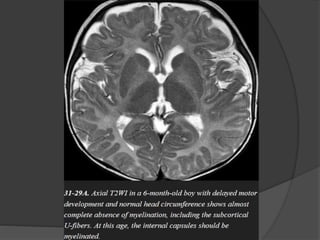

Hypomyelinating Disorders Pelizaeus-Merzbacher Disease X-linkeddisorder that results in nearly complete lack of myelination. One of the most common hypomyelinating disorders. 100% of classic PMD cases occur in males. PMD is typically identified in infants under one year of age. Imaging The typical imaging appearance of PMD is nearly complete lack of myelination. The entire cerebral WM appears strikingly and homogeneously hyperintense on T2WI.

• 55.

Preserved myelin aroundperivascular spaces gives the WM a "tiger" pattern. Hyperintensity of the pyramidal tracts or entire pons is typically present. Progressive WM and cerebellar volume loss are common.